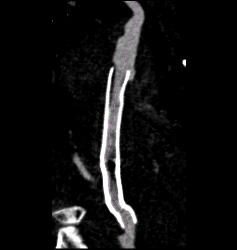

Peripheral Vascular Disease (PVD) With Stent Grafts